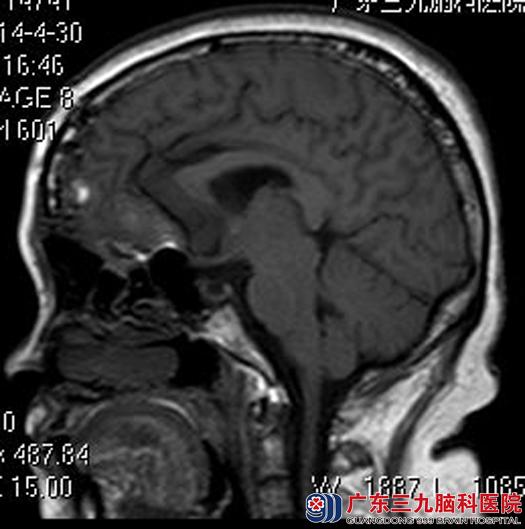

术后月姨睁眼活动正常,不再是朋友们说的“眯眯眼”了。病理结果:脑膜皮细胞型脑膜瘤。

▲手术后